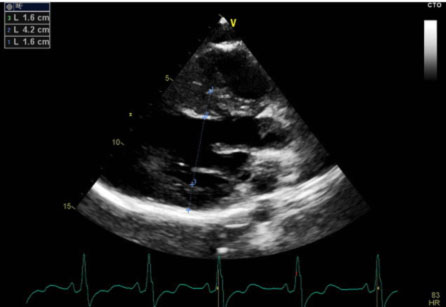

La sindrome di Noonan

“Trattiamo le aritmie cardiache dallo studio dei geni all’ablazione transcatetere“